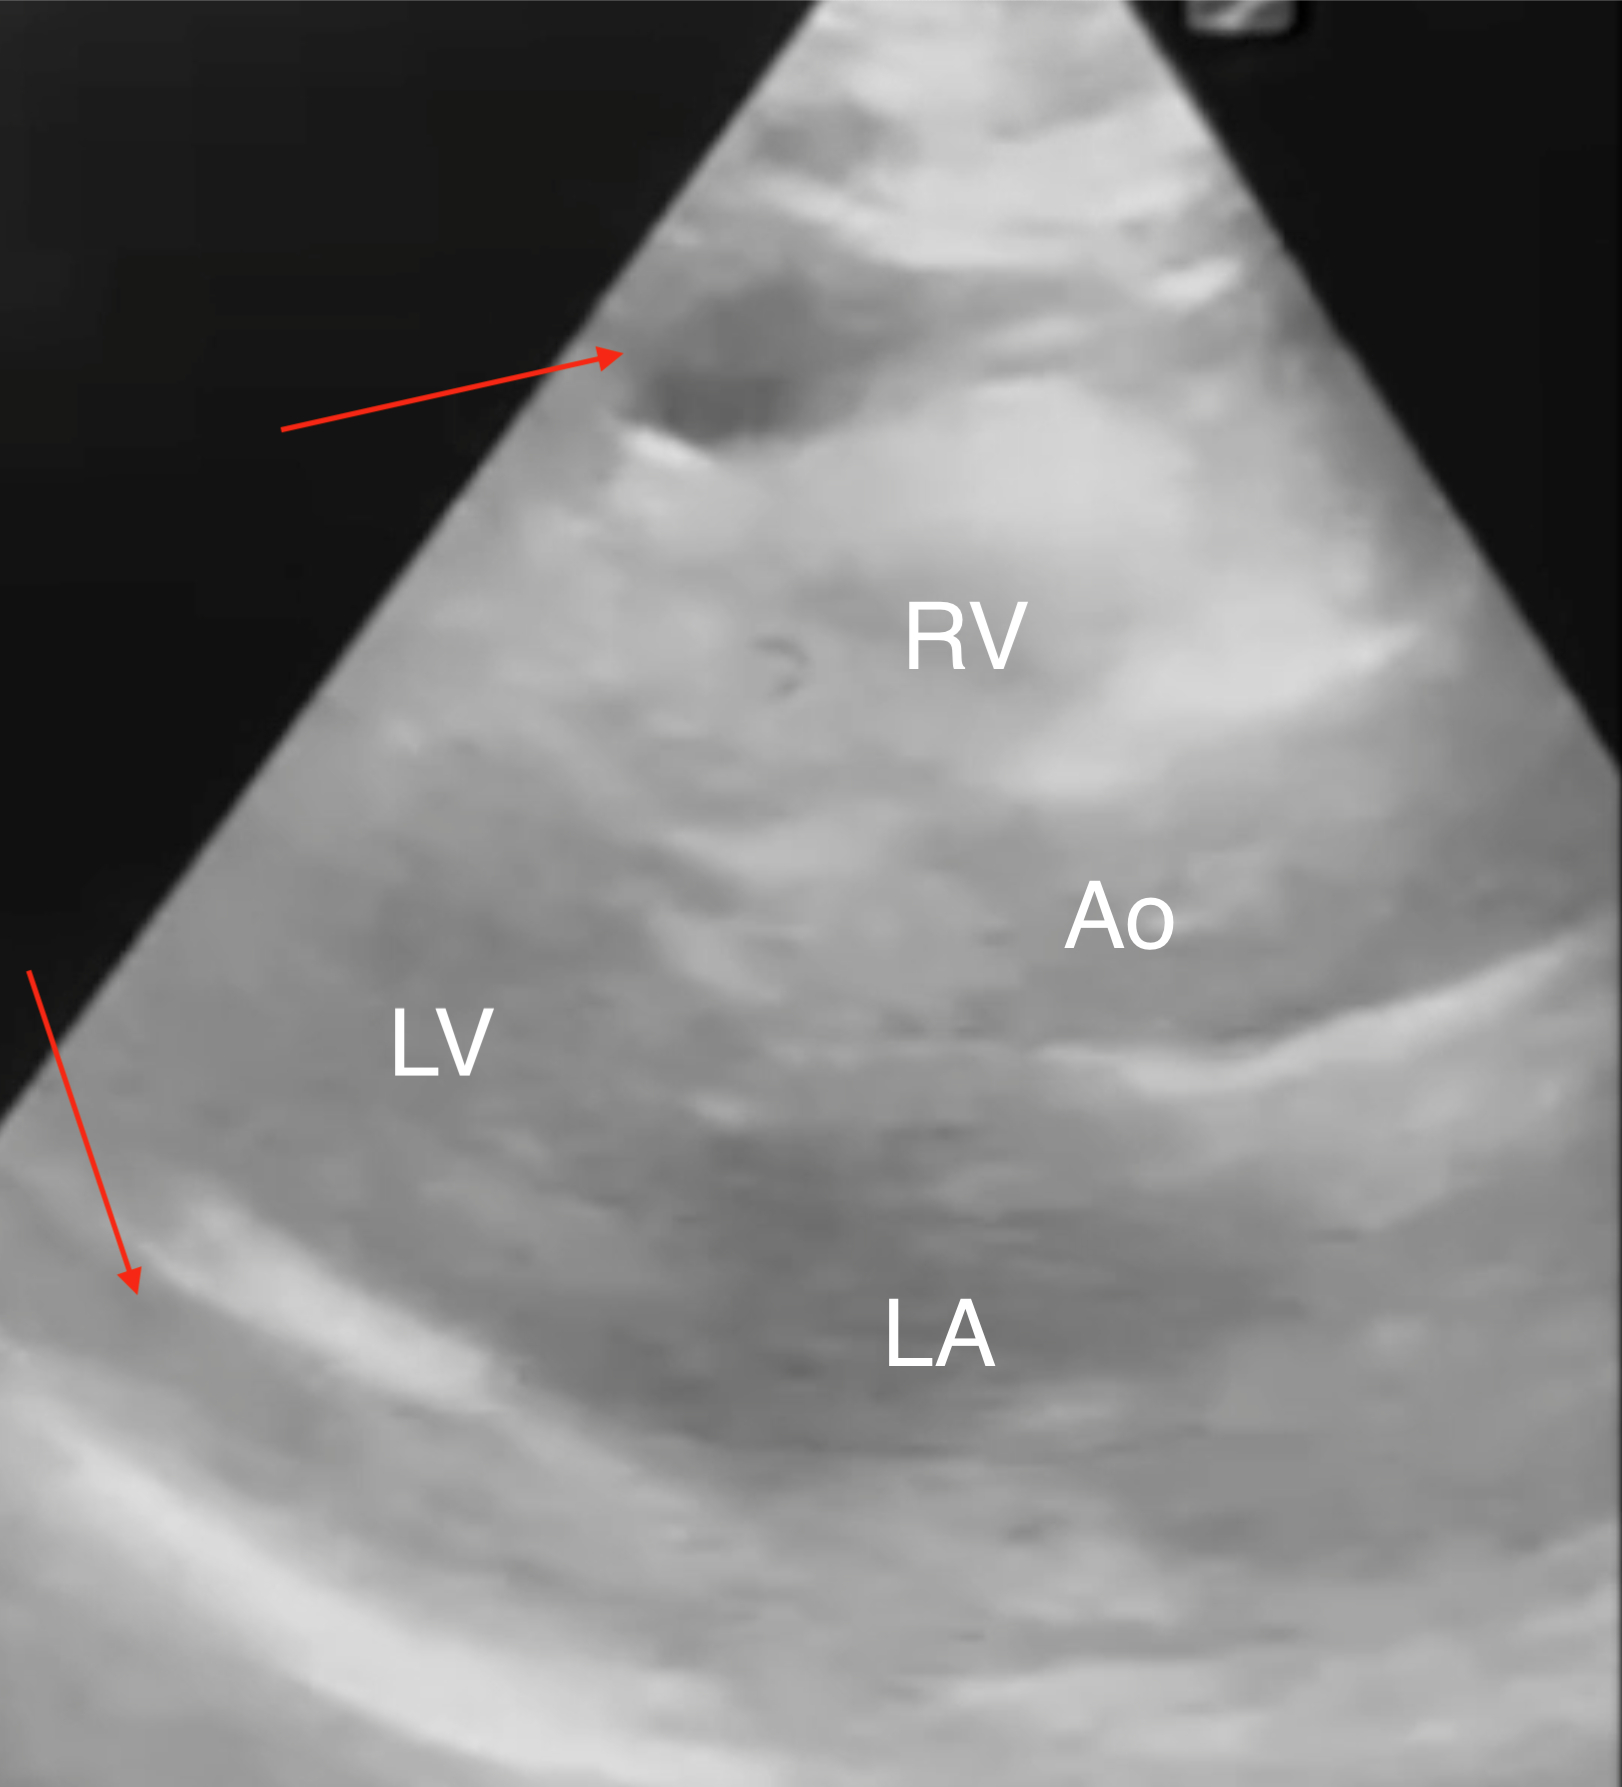

Case: A 61-year-old woman with heart failure with reduced ejection fraction (EF 25%), end-stage renal disease on hemodialysis, and a history of breast cancer presented with a malfunctioning hemodialysis catheter. After unsuccessful local alteplase, interventional radiology performed a left femoral hemodialysis catheter exchange. Within one hour post-procedure, the patient developed syncope, hypotension (60/40 mmHg), tachycardia (120 bpm), and reported chest discomfort, weakness, and lightheadedness. Bedside electrocardiogram showed sinus tachycardia with electrical alternans. Emergent echocardiography revealed a moderate circumferential pericardial effusion with right atrial systolic and right ventricular diastolic collapse, distended inferior vena cava, and marked respirophasic variation of atrioventricular inflow velocities, consistent with cardiac tamponade. Chest radiography suggested the catheter tip abutting the right atrial free wall. The delayed perforation was likely due to catheter migration and erosion. Despite aggressive fluid resuscitation and norepinephrine infusion (up to 35 mcg/hr), the patient remained unstable. Bedside pericardiocentesis drained approximately 700 mL of blood, resulting in rapid hemodynamic improvement and discontinuation of vasopressors within one hour. Computed tomography confirmed the catheter tip’s proximity to the right atrial wall. Cardiothoracic surgery determined that surgical intervention was unnecessary as the perforation had sealed spontaneously.